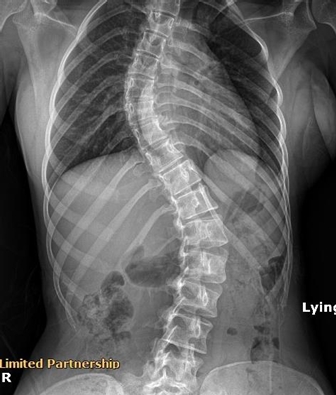

คุณ Neomii

อาการ: กระดูกสันหลังคด (Scoliosis)

"มีอาการปวดหลังเรื้อรังจากกระดูกสันหลังคด หลังมารักษาและปรับโครงสร้างที่นี่ แนวโค้งกระดูกดีขึ้นมาก อาการปวดหายไปเลยค่ะ"

★★★★★